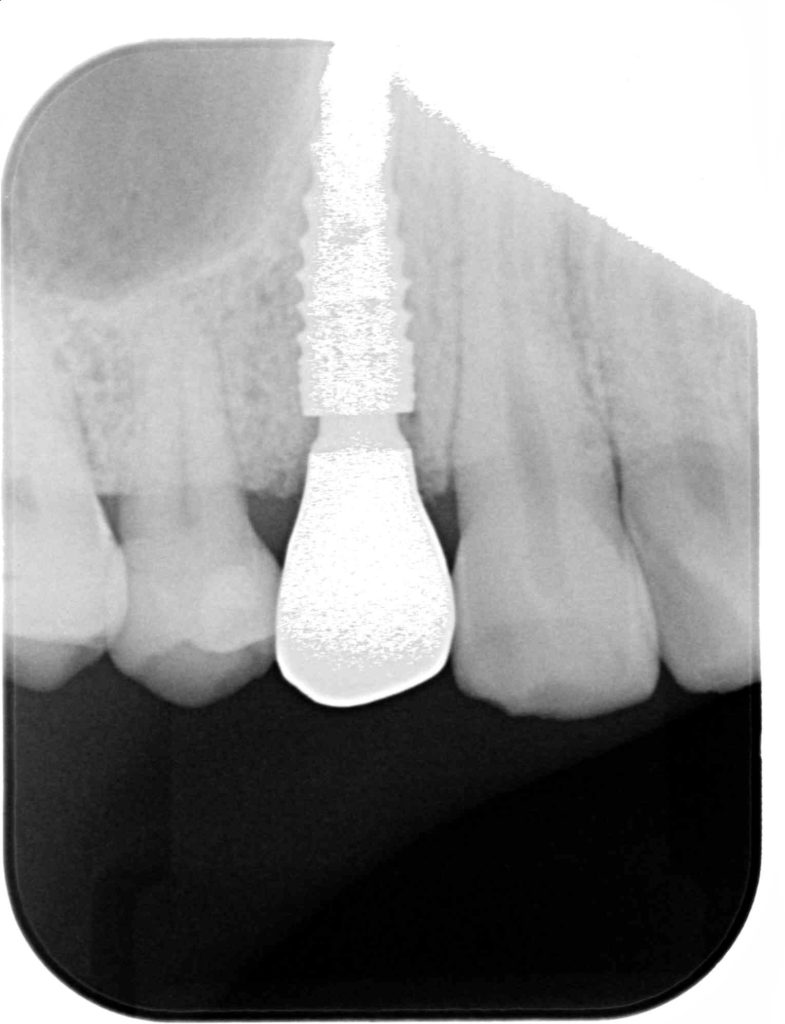

神経がないので痛みというより違和感程度でしたが、抜歯に同意していただき、抜歯と同時にインプラント治療を行い、できるだけ負担を減らし治療期間を短縮する計画を立てました。

この症例にかかる治療期間 約4ヶ月

この症例にかかる費用 約63万円(税別)